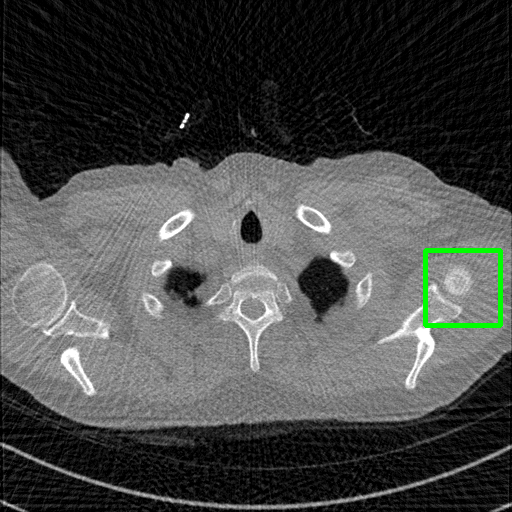

Qualitative comparison. We also visualize the reconstructed images of these methods in Fig. 4 with = [72, 96 ,144] (See more visualizations in Appendix). In all three rows, our DuDoTrans shows better detail recovery, and sparse-view artifacts are suppressed. Further, when decreasing , where raw sinograms are too messy to be restored and low-quality images from FBP are too hard to capture global features, Transformer-based models exhibit reduced performance. The phenomena suggests that we should design suitable structures with the Transformer and CNNs, facing with different cases.

Ground Truth

FBP

FBPConvNet

DuDoNet

ImgTrans

DuDoTrans